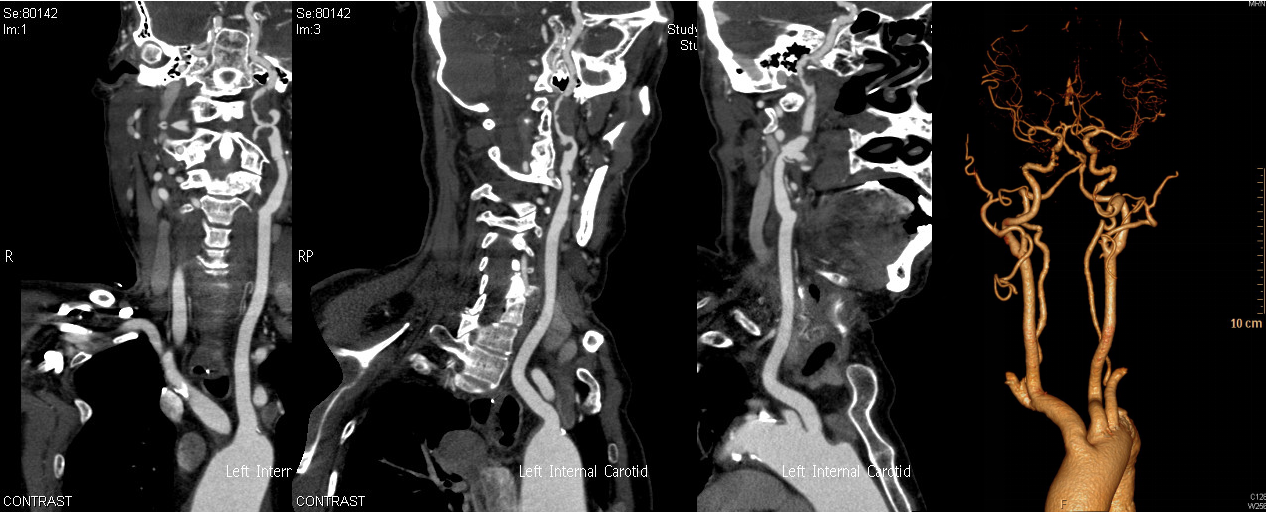

颈动脉CTA

DSA显示ICAO

微导管造影证实MCAO